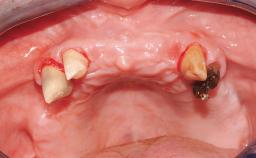

Immediate Loading of Six Implants in the Maxilla and Final Restoration with a Full-Arch CAD/CAM Zirconia FDP

A 63-year-old male patient was referred for a consultation and treatment of partial edentulism in the maxilla. The patient presented with residual anterior teeth and declined a partial removable prosthesis. He reported that the maxillary posterior teeth had been extracted due to mobility and periodontal disease two months before the consultation. The patient’s chief complaint was that his residual maxillary teeth were mobile and that he was unable to chew. The patient’s desire was a stable and comfortable fixed maxillary rehabilitation. The patient was a light smoker (fewer than 10 cigarettes/ day), and his medical history was without significant findings. He was not on any regular medication at the time of consultation. The extraoral examination revealed a normal physiognomy with a correct distribution of the facial thirds. The patient presented a low lip line, and the transition line between teeth and soft tissues was not exposed during a forced smile.